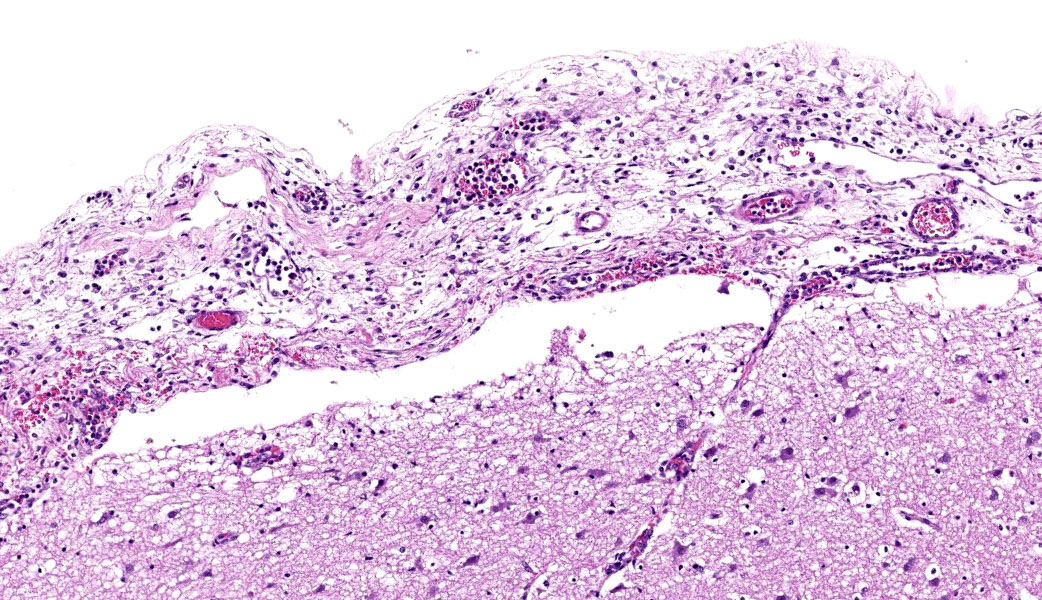

Throughout the cerebral gray matter, small caliber vessel walls were frequently obscured by mild to moderate amounts of eosinophilic, fibrillar, proteinaceous material and hemorrhage. Endothelial cells frequently contained large, eosinophilic, intranuclear inclusions which peripheralize chromatin. Affected vessels were frequently cuffed by moderate numbers of macrophages and lymphocytes, and there were frequent, small areas of hemorrhage spilling into the adjacent tissue. The meninges overlying the cerebellum were moderately expanded by lymphocytes and macrophages, and endothelial cells frequently contained intranuclear inclusions similar to those found in the cerebral vessels.

Severe, multifocal, acute, histiocytic vasculitis and meningitis with cerebral hemorrhage and intranuclear viral inclusions.

Cerebrum: Vasculitis, neutrophilic and lymphocytic, subacute, multifocal to coalescing, marked, with fibrin thrombi, lymphohistiocytic meningitis, and endothelial intranuclear viral inclusions.